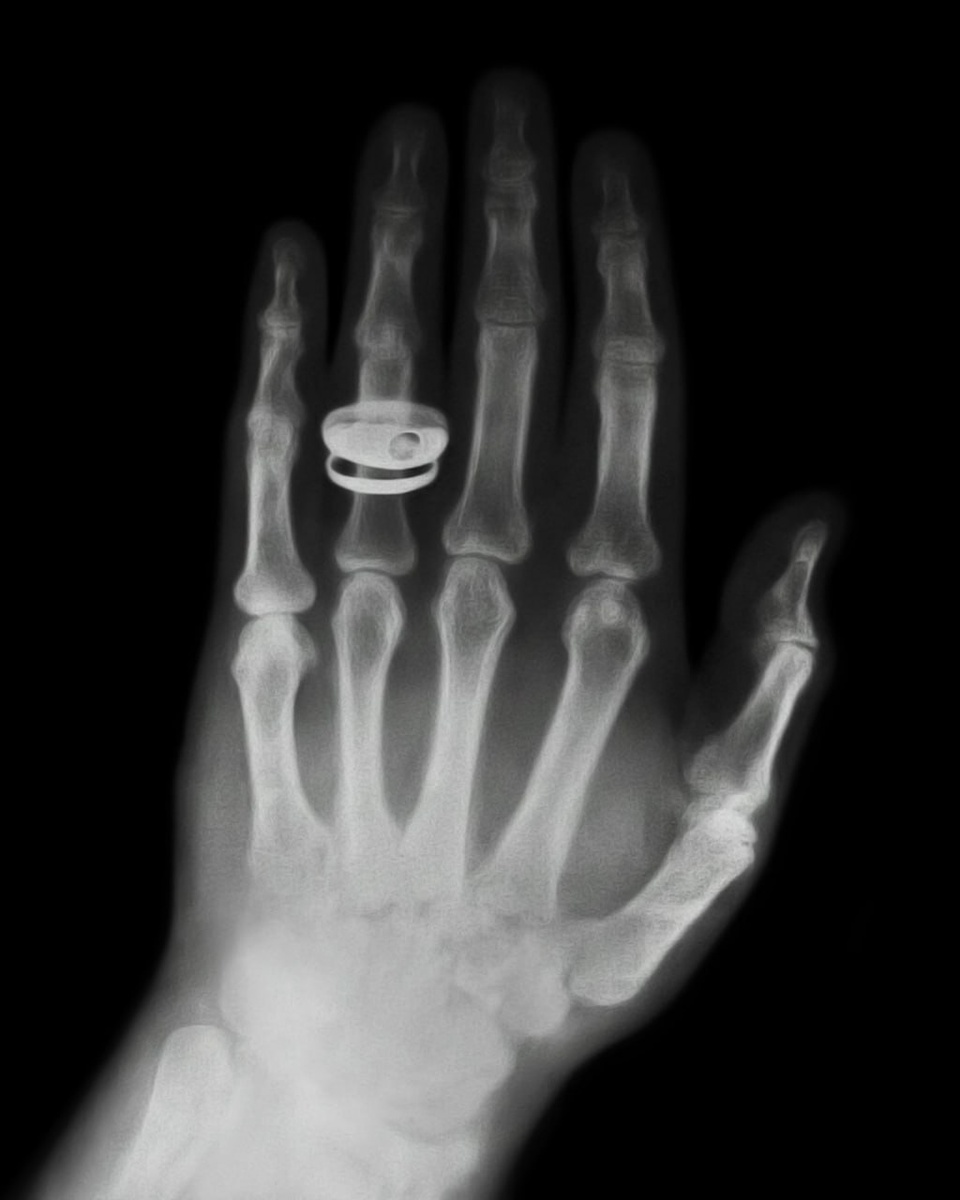

28 декабря 1895 года немецкий физик Вильгельм Конрад Рентген официально представил научному сообществу «Х-излучение».

Ученый отказался патентовать изобретение и заявил: «Моё открытие принадлежит человечеству». Впрочем, лучи он все равно нескромно назвал «рентгеновскими». А вот коллеги высоко оценили разработку - вскоре Рентген стал первым физиком, получившим Нобелевскую премию. Заслуженно!

Забавно: лавры первого в истории рентгеновского снимка достались его жене - Анне Берте Людвиг. И спустя 130 лет у нас есть прекрасная возможность умиляться видом её руки с кольцом.